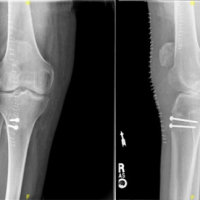

At the 13-month follow-up, the patient presented to the outpatient department with complaints of on-and-off pain in the right hip since past 3 months. Clinical examination revealed terminal restriction of movements with difficulty to sit cross-leg or squat. Radiographic evaluation revealed the reverse Z-effect with broken proximal de-rotation screw, characterized by the medial migration of the lag screw into the hip joint. This finding was concerning for mechanical failure and raised questions about the stability of the fracture site. Serial radiographs and clinical examinations were used to confirm the bone union preoperatively (Fig. 3 and 4).

Given the implant failure, the decision was made to proceed with the removal of the broken PFN. Post-removal radiographs confirmed the absence of the fracture and the integrity of the bony union. The patient was instructed to avoid putting any weight on the affected limb for a period of 6 weeks, after which they might gradually begin to bear weight as tolerated. They were also recommended to schedule regular appointments for clinical and radiological evaluations. Patient was full weight bearing post 3 months with only terminal restriction of movement at hip joint. Patient was followed up for 15 months post-implant removal and showed no complications at the last visit (Fig. 5 and 6).